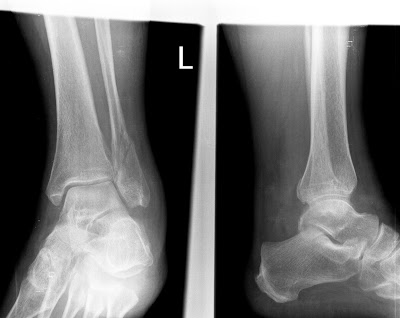

| Weber B – Lauge-Hansen SE III st.

- Lauge-Hansen